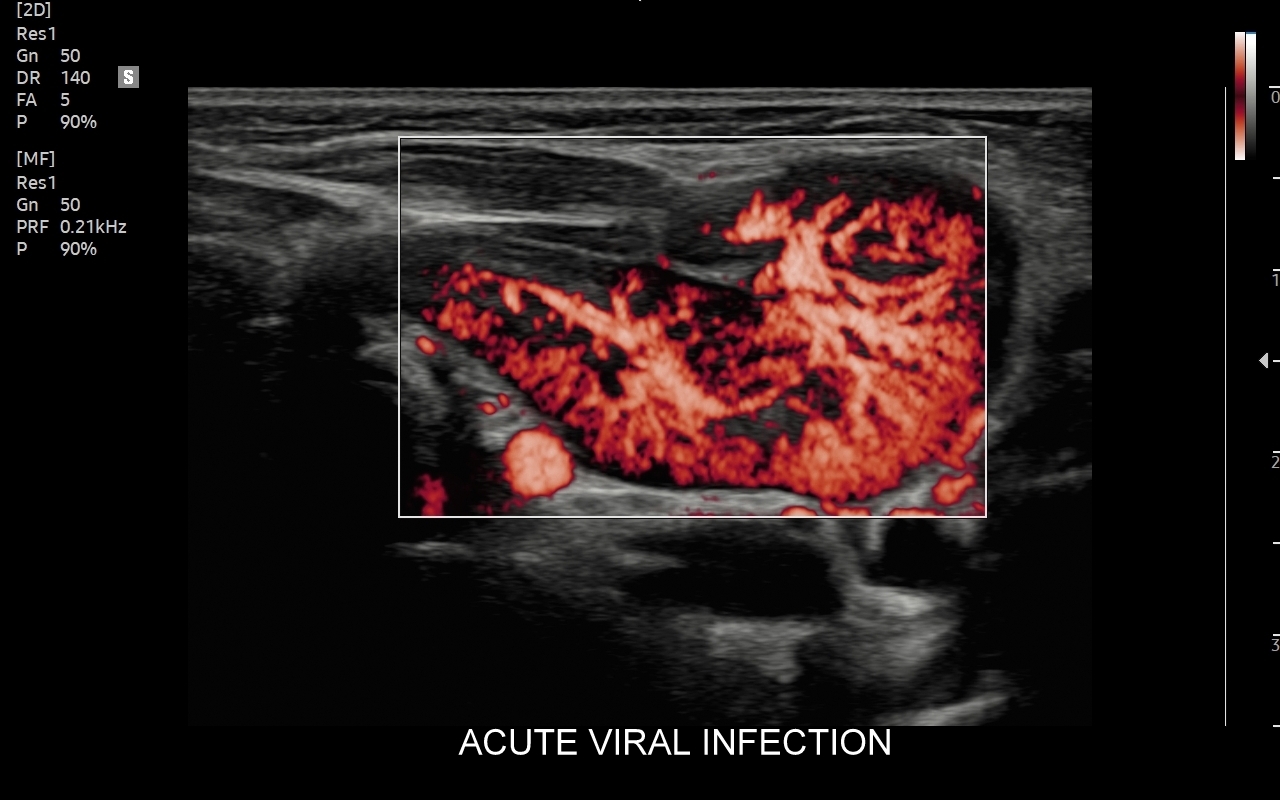

W przebiegu chorób, w których dochodzi do stymulacji układu odpornościowego, węzły limfatyczne ulegają powiększeniu. Przykładami są miejscowe lub uogólnione procesy zapalne i autoimmunologiczne, schorzenia infekcyjne bakteryjne, wirusowe, grzybicze i pasożytnicze. Węzły chłonne powiększać się mogą również w przebiegu białaczek i chłoniaków, a także w trakcie chorób nowotworowych, w których dochodzi do tworzenia przerzutów.

Badanie USG jest podstawową metodą obrazowania węzłów chłonnych. W jego trakcie ocenia się nie tylko wielkość węzłów, lecz także ich kształt, proporcje wymiarów, morfologię, czyli wygląd zewnętrzny oraz strukturę wewnętrzną, ich unaczynienie, spoistość, a także tkanki otoczające. W trakcie interpretacji badania pod uwagę bierze się również zbierany od pacjenta wywiad chorobowy oraz wyniki innych badań obrazowych i laboratoryjnych takich jak morfologia, OB, CRP, żelazo, ferrytyna, TIBC, innych parametrów infekcyjnych, a także onkologicznych. Ultrasonografia węzłów chłonnych jest procedurą bezpieczną i dokładną. W Pracowni dr Szczepańskiego węzły chłonne oceniane są nowoczesną metodą MPUS (multiparametryczne badanie USG), w szczególności z zastosowaniem trybów mikrounaczynienia i elastografii.